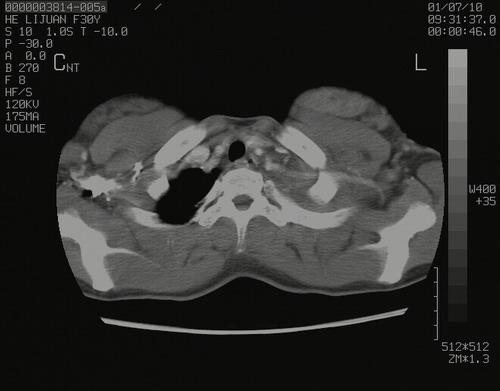

怀孕3个月时(2009-3至4月间),自述突感左侧前后胸疼痛1天,以前胸明显,随后偶感闷痛,余未见异

左肺尖脊柱旁沟肿块,境界清楚,边缘光滑,密度不均,内有多发点片状钙化,考虑良性肿瘤,骨软骨瘤或神经源性肿瘤可能,肺错构瘤不除外。

左后上纵隔见一类圆形肿块影,外侧边界清,密度不均匀,内可见点状钙化影,增强呈不均匀强化,考虑神经源性肿瘤可能。期待病理结果。